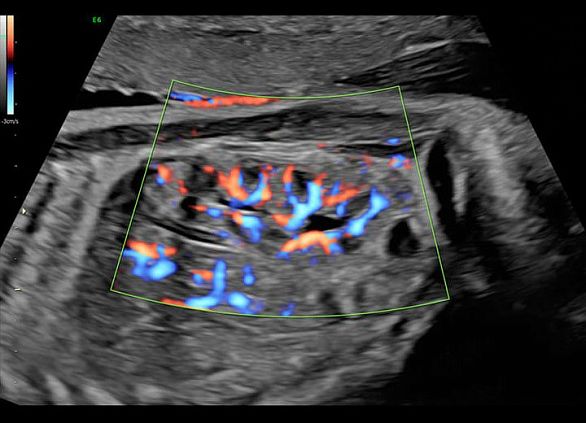

Клинические изображения

- Высокочувствительный допплер (HD-Flow).

УЗИ аппарат Voluson E6 гарантирует превосходное качество визуализации как 2D-режиме, так и при объемной реконструкции в 3D/4D режиме, а также при цветовом допплеровском картировании. Благодаря инновационным инструментам автоматизации и интуитивному интерфейсу пользователя достигается существенное сокращение времени исследований, упрощается труд врача, снижается утомляемость и повышается общая производительность и пропускная способность.

- Высокочувствительный допплер (HD-Flow).

УЗИ аппарат Voluson E6 гарантирует превосходное качество визуализации как 2D-режиме, так и при объемной реконструкции в 3D/4D режиме, а также при цветовом допплеровском картировании. Благодаря инновационным инструментам автоматизации и интуитивному интерфейсу пользователя достигается существенное сокращение времени исследований, упрощается труд врача, снижается утомляемость и повышается общая производительность и пропускная способность.